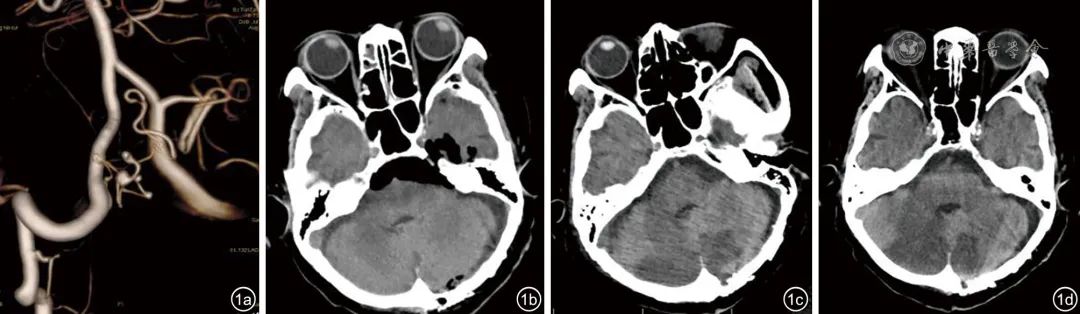

图1 脑动脉瘤患者的中枢神经系统检查。

图a:颅脑DSA示左侧小脑下后动脉瘤;

图b:术后当日颅脑CT示未见明显出血,可见颅腔积气;

图c:术后第3天颅脑CT示双侧小脑半球缺血性改变;

图d:术后第10天颅脑CT示双侧小脑半球缺血性改变

注:DSA为数字减影血管造影